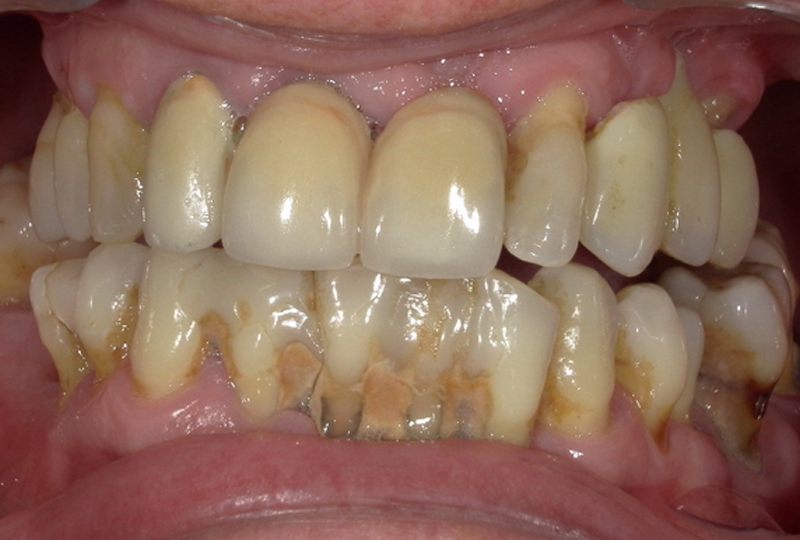

Il paziente di 57 anni, in buono stato di salute generale, si presentava con una vecchia riabilitazione con protesi fissa superiore, con i pilastri dentali a supporto delle protesi e i denti dell’arcata inferiore con un’elevata compromissione parodontale (Figure 1,2).

Da una prima analisi estetica, nonostante la dimensione verticale fosse mantenuta in massima intercuspidazione, si presentava la necessità di spostare la linea mediana, e di recuperare l’asse dentale molto inclinato rispetto al piano di Camper e al piano frontale.